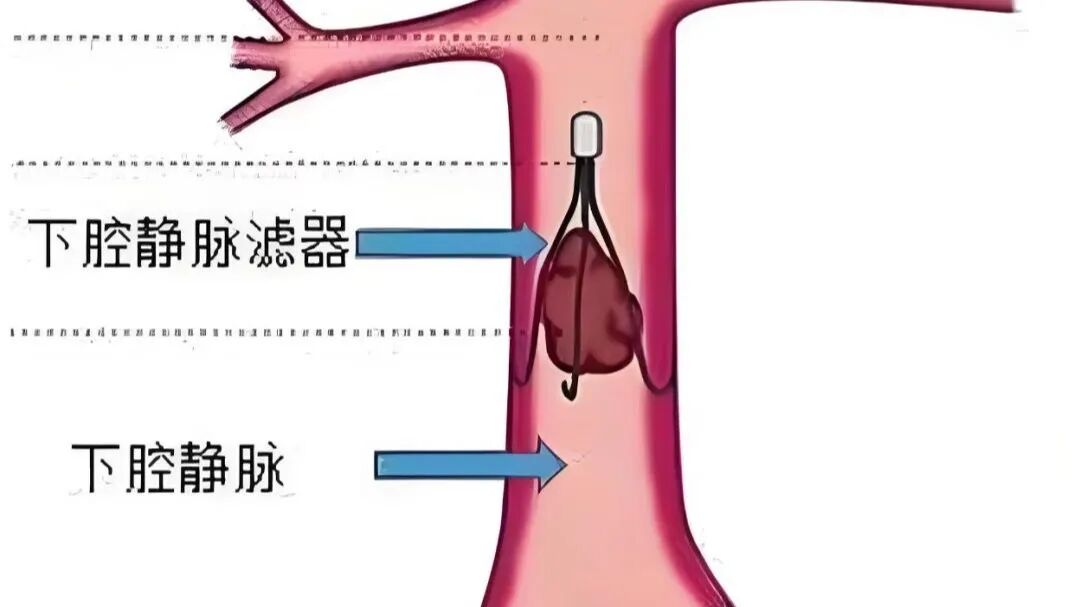

下腔静脉滤器植入术是一种通过介入手段在患者下腔静脉内放置滤器,以防止下肢深静脉血栓脱落并随血流进入肺动脉,造成肺动脉栓塞的手术方法,它就像一个“滤网”,能够拦截可能脱落的血栓,降低肺动脉栓塞的风险。

腿上的血栓脱落后会随静脉血流往上行走,经过腹部到胸部,进入心脏,最终到达肺部(下肢深静脉——髂静脉——下腔静脉——右心房——右心室——肺动脉)。在下腔静脉安置一个过滤器,血流可通过,而血栓被拦截不能通过,就可以完美解除肺栓塞风险。

因此,下腔静脉滤器(IVCF)是为预防下肢深静脉和盆腔静脉丛内血栓脱落引起肺动脉栓塞而设计的一种装置,该装置能在保持下腔静脉血流通畅的同时,可有效拦截血栓,防止肺栓塞的发生。